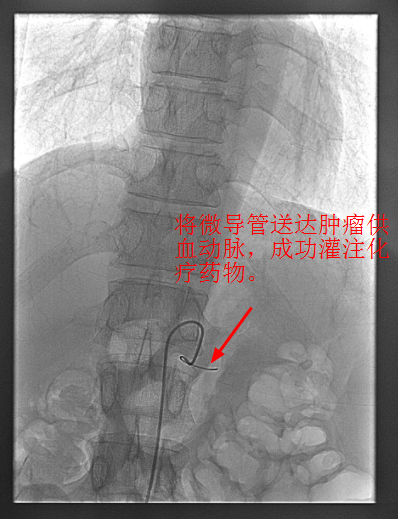

4月30日下午,李旭丹主任與胡志華主任上台實施介入化療術,在DSA造影下,清晰可見胰腺腫瘤的供血動脈,專家們将微導管經股動脈穿刺送達瘤體的供血動脈,成功将化療藥物灌注至瘤體,順利完成手術。術後,患者症狀明顯好轉,并于5月4日順利出院。

李旭丹主任介紹,介入灌注化療,因其能準确定位腫瘤供血動脈,将藥物直接送達瘤體,能更好殺滅癌細胞,且副作用小,在胰腺癌的治療中有着非常明顯的優勢,能爲患者赢得更多的生存機會。